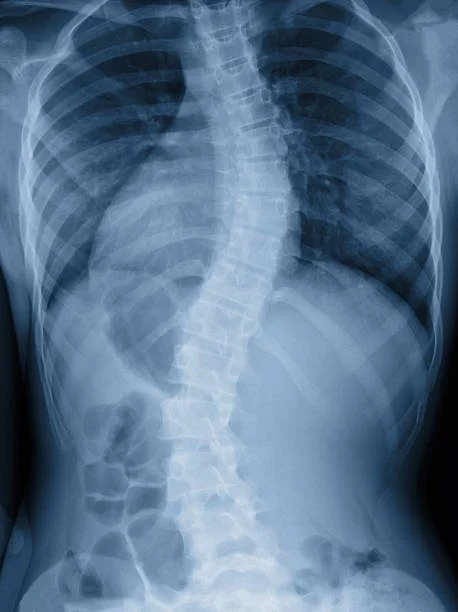

Scoliosis is a lateral curvature of the spine — measured in degrees using a Cobb angle on X-ray — that causes the spine to curve sideways and often rotate. The most common form is idiopathic adolescent scoliosis, which typically develops during growth spurts in children aged 10–18. Adults can also develop scoliosis through degenerative changes or as untreated adolescent curves progress with age.

Cobb Angle X-Ray Analysis

We take weight-bearing spinal X-rays and perform a full Cobb angle measurement — establishing your curve's degree, location, and rotational component. This is your baseline. We track it to measure real structural change over time, not just symptom relief.